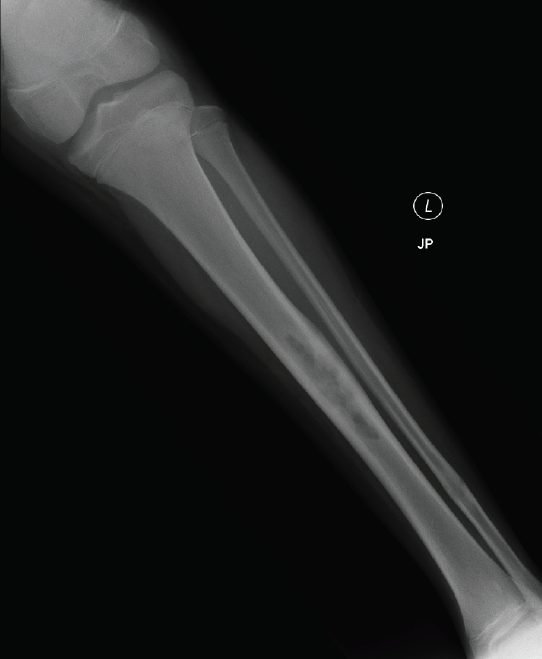

A radiograph of the left leg revealed localized cortical thickening on the anterior midshaft of the tibia, within which were multiple areas of radiolucency (Figure 2). Results of chest radiography were normal. Laboratory results revealed a white blood cell count of 6,100/µL, a hemoglobin level of 14.2 g/dL, a hematocrit of 40.6%, an erythrocyte sedimentation rate (ESR) of 24 mm/h, and a C-reactive protein (CRP) level of 1.66 mg/dL. No immunologic testing was performed. He underwent open biopsy and culture of the tibial lesion.

Figure 2 – Multiple areas of radiolucency on a radiograph of the boy’s left leg indicated cortical thickening on the anterior midshaft of the tibia.